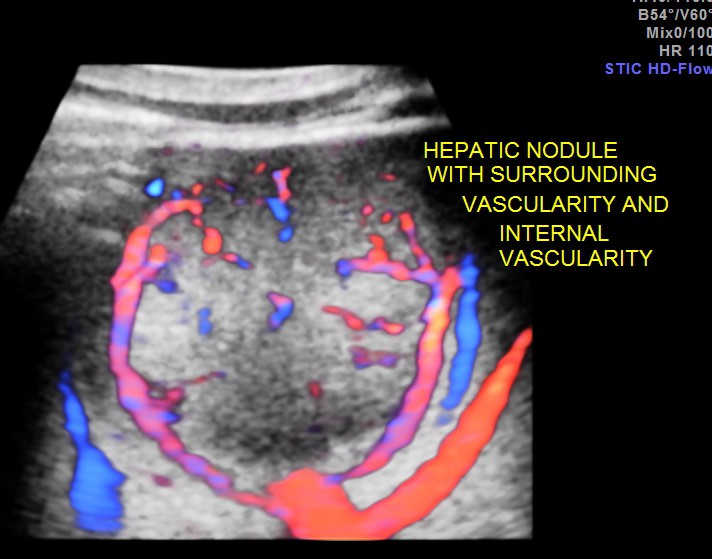

3 d reconstruction shows the solid nature and vascularity around and within the nodule.

The appearance of this nodule was suggestive of a metastatic nodule with the increased vascularity around and within.